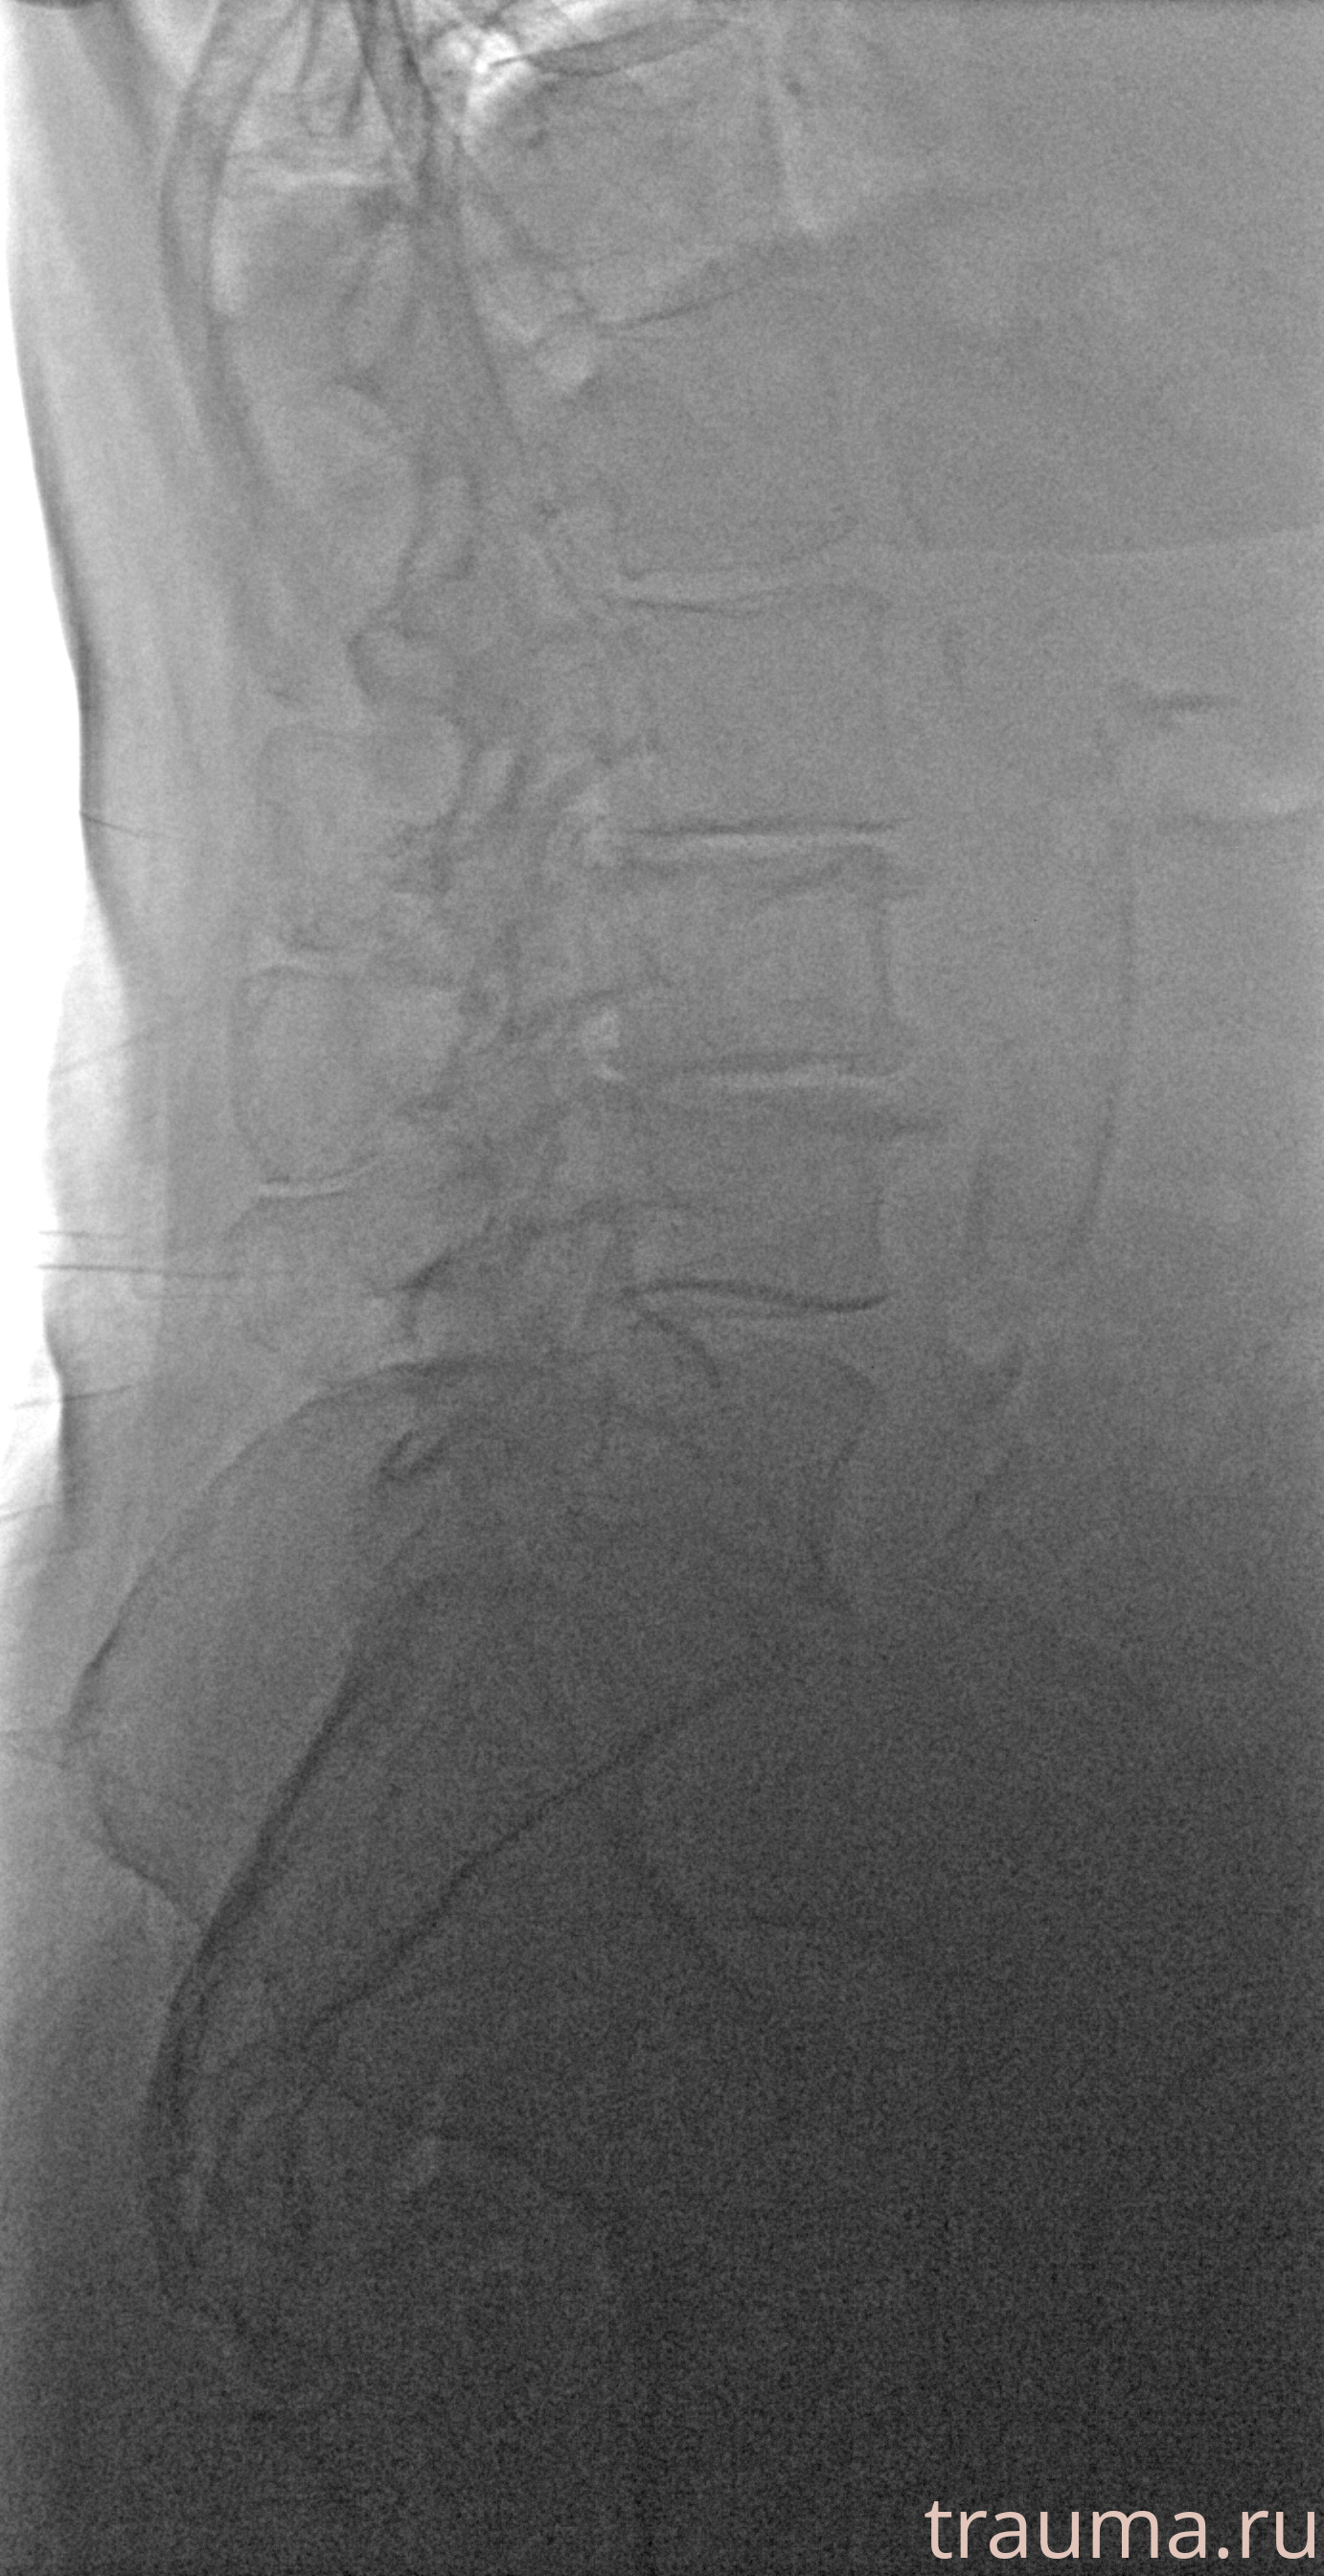

Рентген на дому: по вашему адресу приезжает врач-рентгенолог, травматолог-ортопед с мобильным рентгеновским аппаратом, проводит диагностику травмы или заболевания, делает необходимые рентгенограммы, дает рекомендации по дальнейшему лечению. Получить качественные снимки в домашних условиях возможно благодаря уникальной методике, разработанной МосРентген Центром для института  Склифосовского

при переломе шейки бедра и пневмонии от компании МосРентген Центр - партнера Института имени Склифосовского